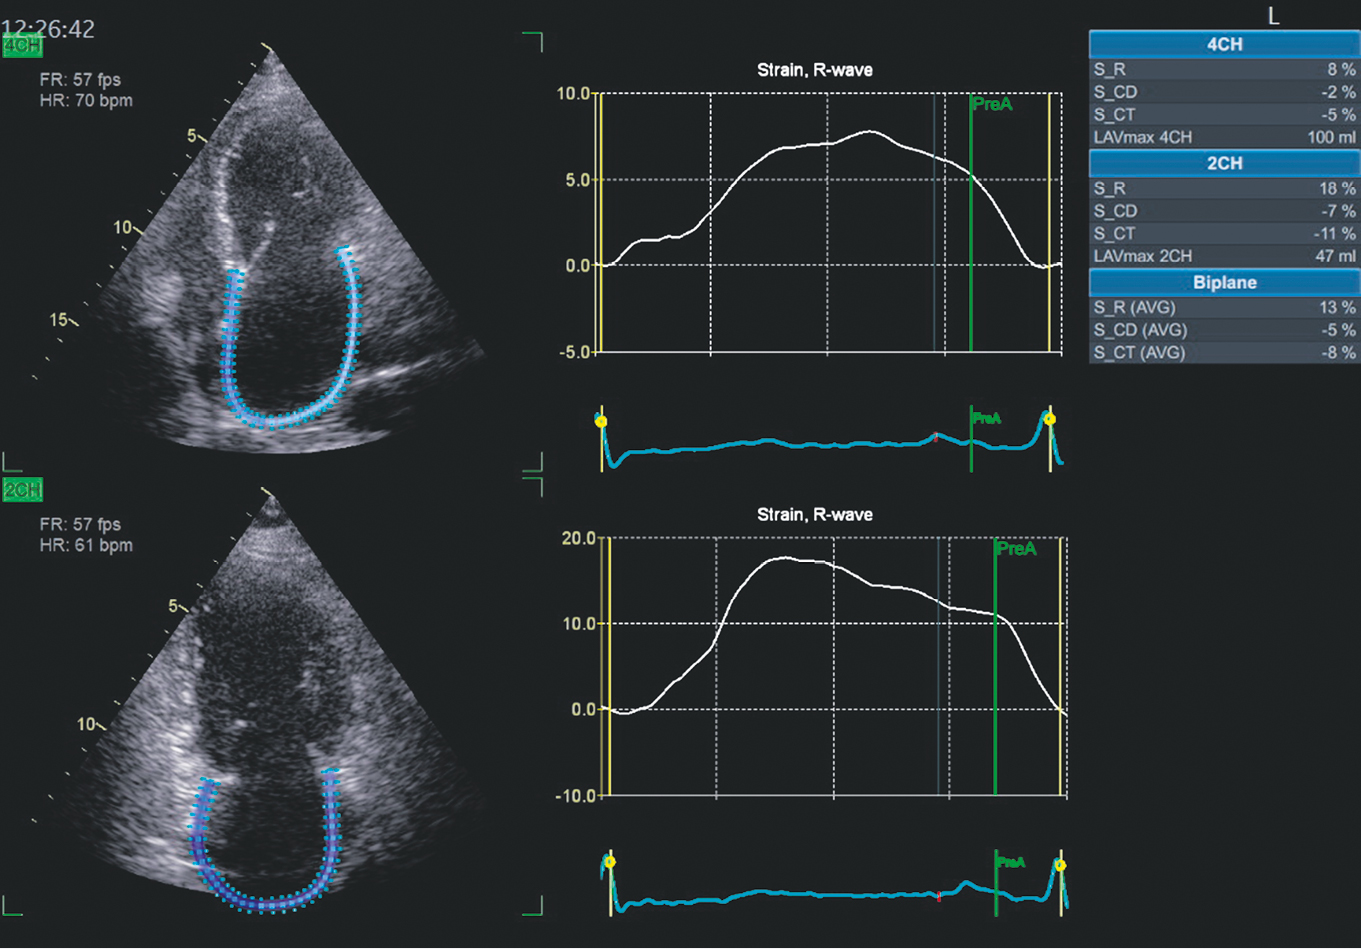

The control EchoCG demonstrated positive dynamics, with an increase in EF to 49%, decrease in EDVI to 45 mL/m2, LAVI remained the same (68 ml/m2), PASP decreased to 29 mmHg. Diastolic function parameters exhibited improvement, with VE/VA = 1.1 and VE/Em ratio (mean) = 10.3 (grade 1 diastolic dysfunction). Longitudinal deformation of the LV myocardium was determined (in the 2D-strain mode). It was significantly impaired, with a value of −15% (which is below the normal range of −18%). Maximum myocardial deformation disturbances were observed in the hypertrophied IVS (the zone is colored pale pink in Fig. 2).

Fig. 2. Bull’s eye format of peak global longitudinal strain of the left ventricular myocardium. Explanation in the text

A control EchoCG was performed in February 2024. For other parameters the following results were obtained: EDVI (48 mL/m2), LAVI (63 mL/m2), PASP (25 mmHg), VE/VA = 1.1, and VE/Em (mean) = 10.0 were noted. The dynamics of key EchoCG indices are presented in Table 2. Unfortunately, the global longitudinal LV myocardial strain did not improve, remaining at the level observed in 2022.

The HCMP is diagnosed based on the presence of LV wall thickening, which is extremely rare on the right ventricle. This thickening cannot be explained by increased hemodynamic load, which includes arterial hypertension and valvular heart diseases. In the proband, the quantitative criterion of myocardial thickness of ≥15 mm is considered diagnostic [1, 3, 9]. Since 2002 until 2021 the patient exhibited the classic phenotype of nonobstructive HCMP, which is characterized by pain syndrome and various rhythm disturbances. HCMP-related heart failure is more often associated with diastolic dysfunction, primarily in the early disease stages. In some patients (5%–8% of those suffering from HCMP), a systolic component may be added due to the burnout phenomenon, which is characterized by a decrease in LV EF ≤50%, LV wall thinning, and LV cavity dilation [3, 4]. The term “burnout HCMP” has been proposed to distinguish this phenotype, which is novel for the patient and emerged during disease progression, from the phenotype at the time of diagnosis [4]. Currently, no clear criteria can be used to predict the transition from the hypertrophic stage to the burnout phase. However, several potential factors have been identified, including certain mutations of genes encoding the synthesis of sarcomere proteins, family history of a terminal dilated stage of HCMP, AF, and degree of late signal enhancement by gadolinium, which reflects the severity of fibrosis on cardiac MRI [3, 4]. EF is not an optimal method for the early detection of the burnout phenomenon. Changes of myocardial longitudinal strain over time allows an unfavorable prognosis assumed. In recent years, echocardiographic assessment of myocardial longitudinal strain has become a widely used diagnostic tool. D.M. Adamczak et al. revealed an association between myocardial longitudinal strain and burnout [10]. Longitudinal LV myocardial strain was assesed in the patient at the stage of EF restoration in 2022 and 2024. It appeared to be reduced and did not improve significantly in 2024 compared with 2022, whereas EF increased from 49% to 55%. Unfortunately, this parameter was not determined before 2022.